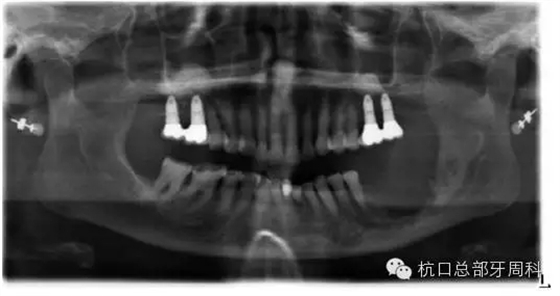

被診斷為種周炎時(shí)全景片 2011

111.webp.jpg